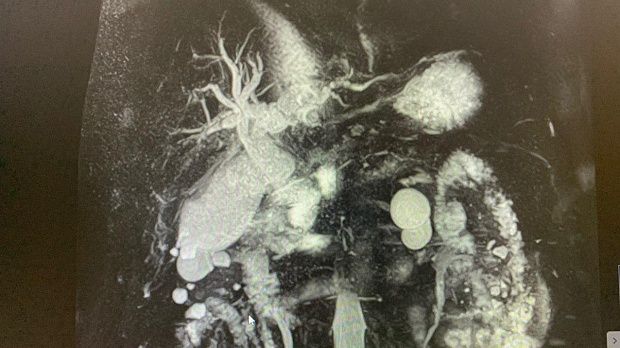

2)Биохимический анализ крови: Билирубин- 82,4 , прямой- 47,5 АЛТ- 92 , АСТ-136 , С-реактивный белок -44,4 скорость клубочковой фильтрации- 45 . МРТ: внутри- и внепеченочные протоки расширены , общий печеночный проток до 18 мм, холедох до 14 мм, в просвете конкременты до 14 мм. Заключение: Холедохолитиаз . Билиарная гипертензия.

На следующий день произведена ретроградная холангиопанкреатография.

Отмечатся юкстапапиллярное расположение большого дуоденального сосочка тип-3. Канюляция папиллотомом pull-type ,контрастирование водорастворимым контрастом .

Рентгенологическая картина расширенния желчных протоков и наличие конкрментов в холедохе. Произведена эндоскопическая ограниченная папиллосфинктеротомия, отмечалось поступление темной желчи. Ревизия корзиной Дормия дали основания полагать ,что конкременты плотной консистенции.